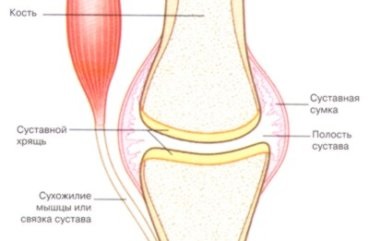

A szerkezet az emberi ízületek nem könnyű, és van osztva a következő fő elemeket tartalmazza: az üreg, a kapszula felülete, ízületi folyadék, porc, szalagokat és izmokat. Röviden beszélni minden alább.

- A izületi üreg - egy slot-alakú tér, amely ebben az esetben légmentesen tömíthető, és tele van az ízületi folyadékban.

- ízületi tok - áll kötőszövet, ami körülveszi a csontokat a végén. A kapszulát alakítunk kívül a szálas membrán belsejében a membrán egy vékony szinoviális (ízületi folyadék forrás).

- Ízületi felület - egy speciális alakja, az egyik ezek közül konvex (más néven fej), és a második yamkoobraznaya.

- Ízületi folyadékban. Fő feladata, hogy kenést és felületi nedvesedés, is végez fontos szerepet a csere folyadékok. Ez egy puffer terület különböző mozgások (remegés, rándulások, tömörítés). Ez biztosítja mind a csúszó és különbségek a csont üregek. Számának csökkentése az az ízületi hártya vezet számos betegség, csont deformitások, veszteség az emberi kapacitás normális fizikai aktivitás és ennek következtében, még akkor is letiltása.

- Porcszövet (vastagsága 0,2-0,5 mm). csont felület borítja porc, a fő funkciója az értékcsökkenés járás közben, sportolás. porc anatómiája képviselik szálak kötőszövet, amely tele van folyadékkal. Ő viszont táplálja a porcot, nyugalomban és mozgásban termel folyadékot kenéséhez csontok.

- Szalagokat és izmokat - támogatja az épület egy részét, de nélkülük nem lehet a szokásos funkciók az egész szervezet. A rendszer segítségével a szalagok csontok vannak rögzítve, anélkül, hogy akadályozná a mozgását minden amplitúdó miatt rugalmasságát.